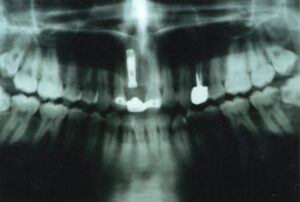

Casi Clinici: corone su impianti in titanio

Un impianto in titanio è costituito da 2 parti: una parte filettata detta fixture che va inserita nell’osso ed un’altra parte detta moncone o abutment che è il pilastro su cui verrà fissata la capsula che puo essre cementata o avvitata